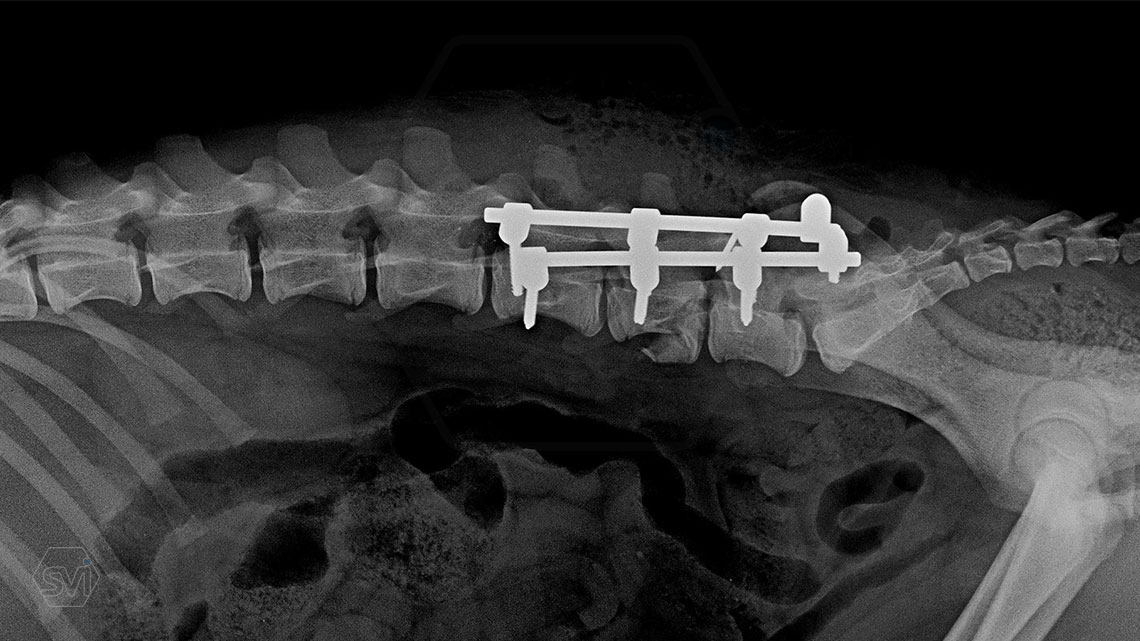

L6 vertebral body fracture fixation with 2.7-mm SOP-LC system

A mixed breed dog, 13 kg, about 8 months old, suffered a car accident and had a fracture of the L6 vertebral body with a mild displacement. (As an additional finding, there was also a fracture of the right radius ulna.) After the accident, his neurological condition was promising.

We performed a laminectomy of L7 and then performed fixation with a 4-4 clamp, bilateral 2.7-mm SOP-LC system. Control x-rays were taken at 6 and 12 weeks after surgery. Based on the video, in our opinion, the dog has recovered… :)